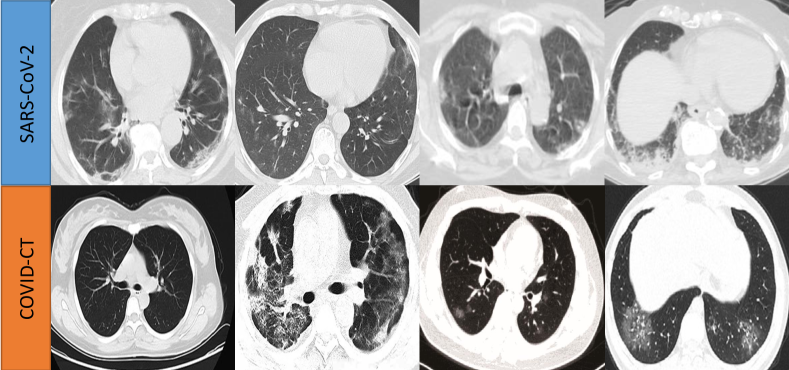

Refer to caption

Figure 1: The CT images of COVID-19 patients from two different clinical centers, showing data heterogeneity on the appearance and contrast.

A considerable amount of data-driven methods have been rapidly developed within this scenario, where the high accuracy is typically attributed to a collected large-scale training database [2, 3, 4], however, this is difficult to generally achieve in practice. Instead, to mitigate the insufficiency of single-site data amount, aggregating the CT imaging data from different hospitals is desired for establishing a cross-site learning scheme. For instance, Di et al. [5] proposed a hypergraph model with multi-site pneumonia data to achieve rapid identification of COVID-19 cases. Wang et al. [6] developed COVID-Net using data collected from different repositories to build an accurate deep learning classifier for X-Ray images. However, so far, a major limitation of these works is their negligence of the data heterogeneity across different clinical centers with various imaging conditions (e.g., scanner vendors, imaging protocols, etc). As illustrated in Fig. 1, the CT slices of COVID-19 patients from two different public datasets present apparently different image contrasts. This could potentially affect the model ability to extract robust and general representations as assumed. Previous studies on other medical imaging applications [7, 8, 9] have frequently observed that straight-forward joint learning with such heterogeneous datasets only brings limited improvement, or even sometimes underperforming individual models trained on a single dataset.

The CT images used in this study present notable appearance differences for COVID-19 patients across different severity. For examples as shown in Fig. 1, the mild patient may only contain a small lesion while severe patient can be infected almost in whole lung scope. Such large variance within the input space further presents difficulties for the model to explore a robust optimal solution from heterogeneous COVID-19 datasets. To address this problem, we expect a smooth learning process to facilitate the model optimization to reach a relatively robust solution. To this end, we propose to improve the COVID-Net learning strategy by adjusting learning rate more smoothly in a cosine annealing manner [31]. Specifically, denoting the total training epoch as T𝑇T, the learning rate at a current epoch t𝑡t is calculated as follows: